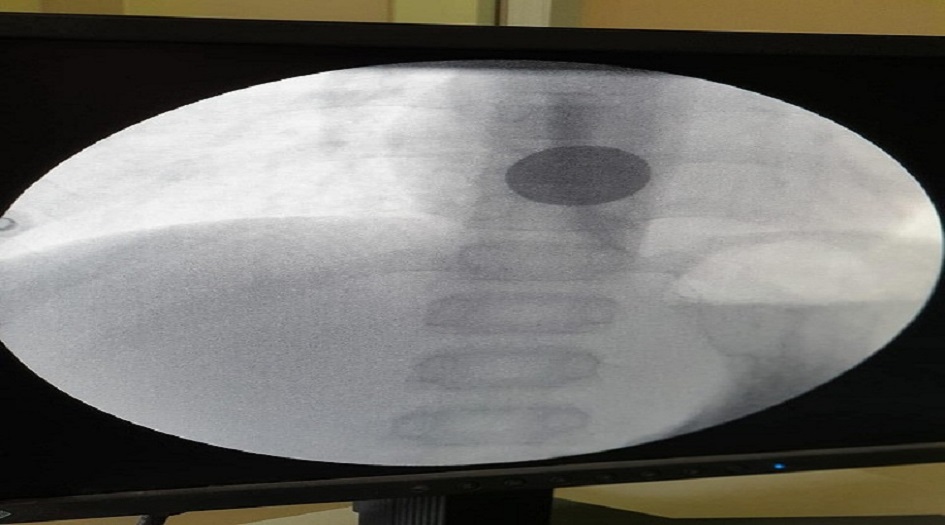

وتابع انه "بعد اخذ الفحوصات والأشعة اللازمة تبين مكان القطعة المعدنية لجئنا لاستخراجها بواسطة الناظور، وهي تقنية جديدة لاتعرض المريض لفتح البطن وتكون سريعة ولا تبعات الإفاقة من بعد العملية".